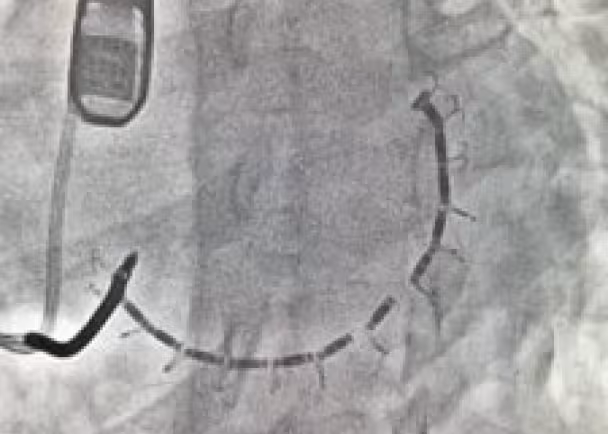

During the procedure, a catheter is guided through the aortic valve to reach the left ventricle. A series of anchors are implanted in the left ventricle heart wall below the mitral valve. A cable connects the anchors and is cinched in place. Once cinched, the left ventricular size is reduced, the heart wall is strengthened, and symptoms of heart failure and FMR are reduced.